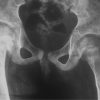

The anteroposterior (AP) radiogram of the whole spine revealed no obvious scoliosis, with bone maturity of Risser Grade 4 (Fig. 1a). The lateral radiogram of the whole spine showed hypoplasia of the anterior portion of the L2 vertebral body with a sagittal vertical axis (SVA) of −60 mm (Fig. 1b). The AP diameters measured at the center of the L1, L2, and L3 vertebral bodies were 36 mm, 27 mm, and 41 mm, respectively. The spinal parameters measured in the lateral radiogram were as follows: Thoracic kyphosis (TK) at T5–12, 17°; local kyphosis at L1–3, 23°; lumbar lordosis (LL) at L1–S1, 38°; LL at L3–S1, 59°; and pelvic incidence (PI), 34° (Fig. 1b). In the dynamic lateral radiograms, local kyphosis at L1–3 was 23° in the extended position (Fig. 2a) and 44° in the flexed position (Fig. 2b).